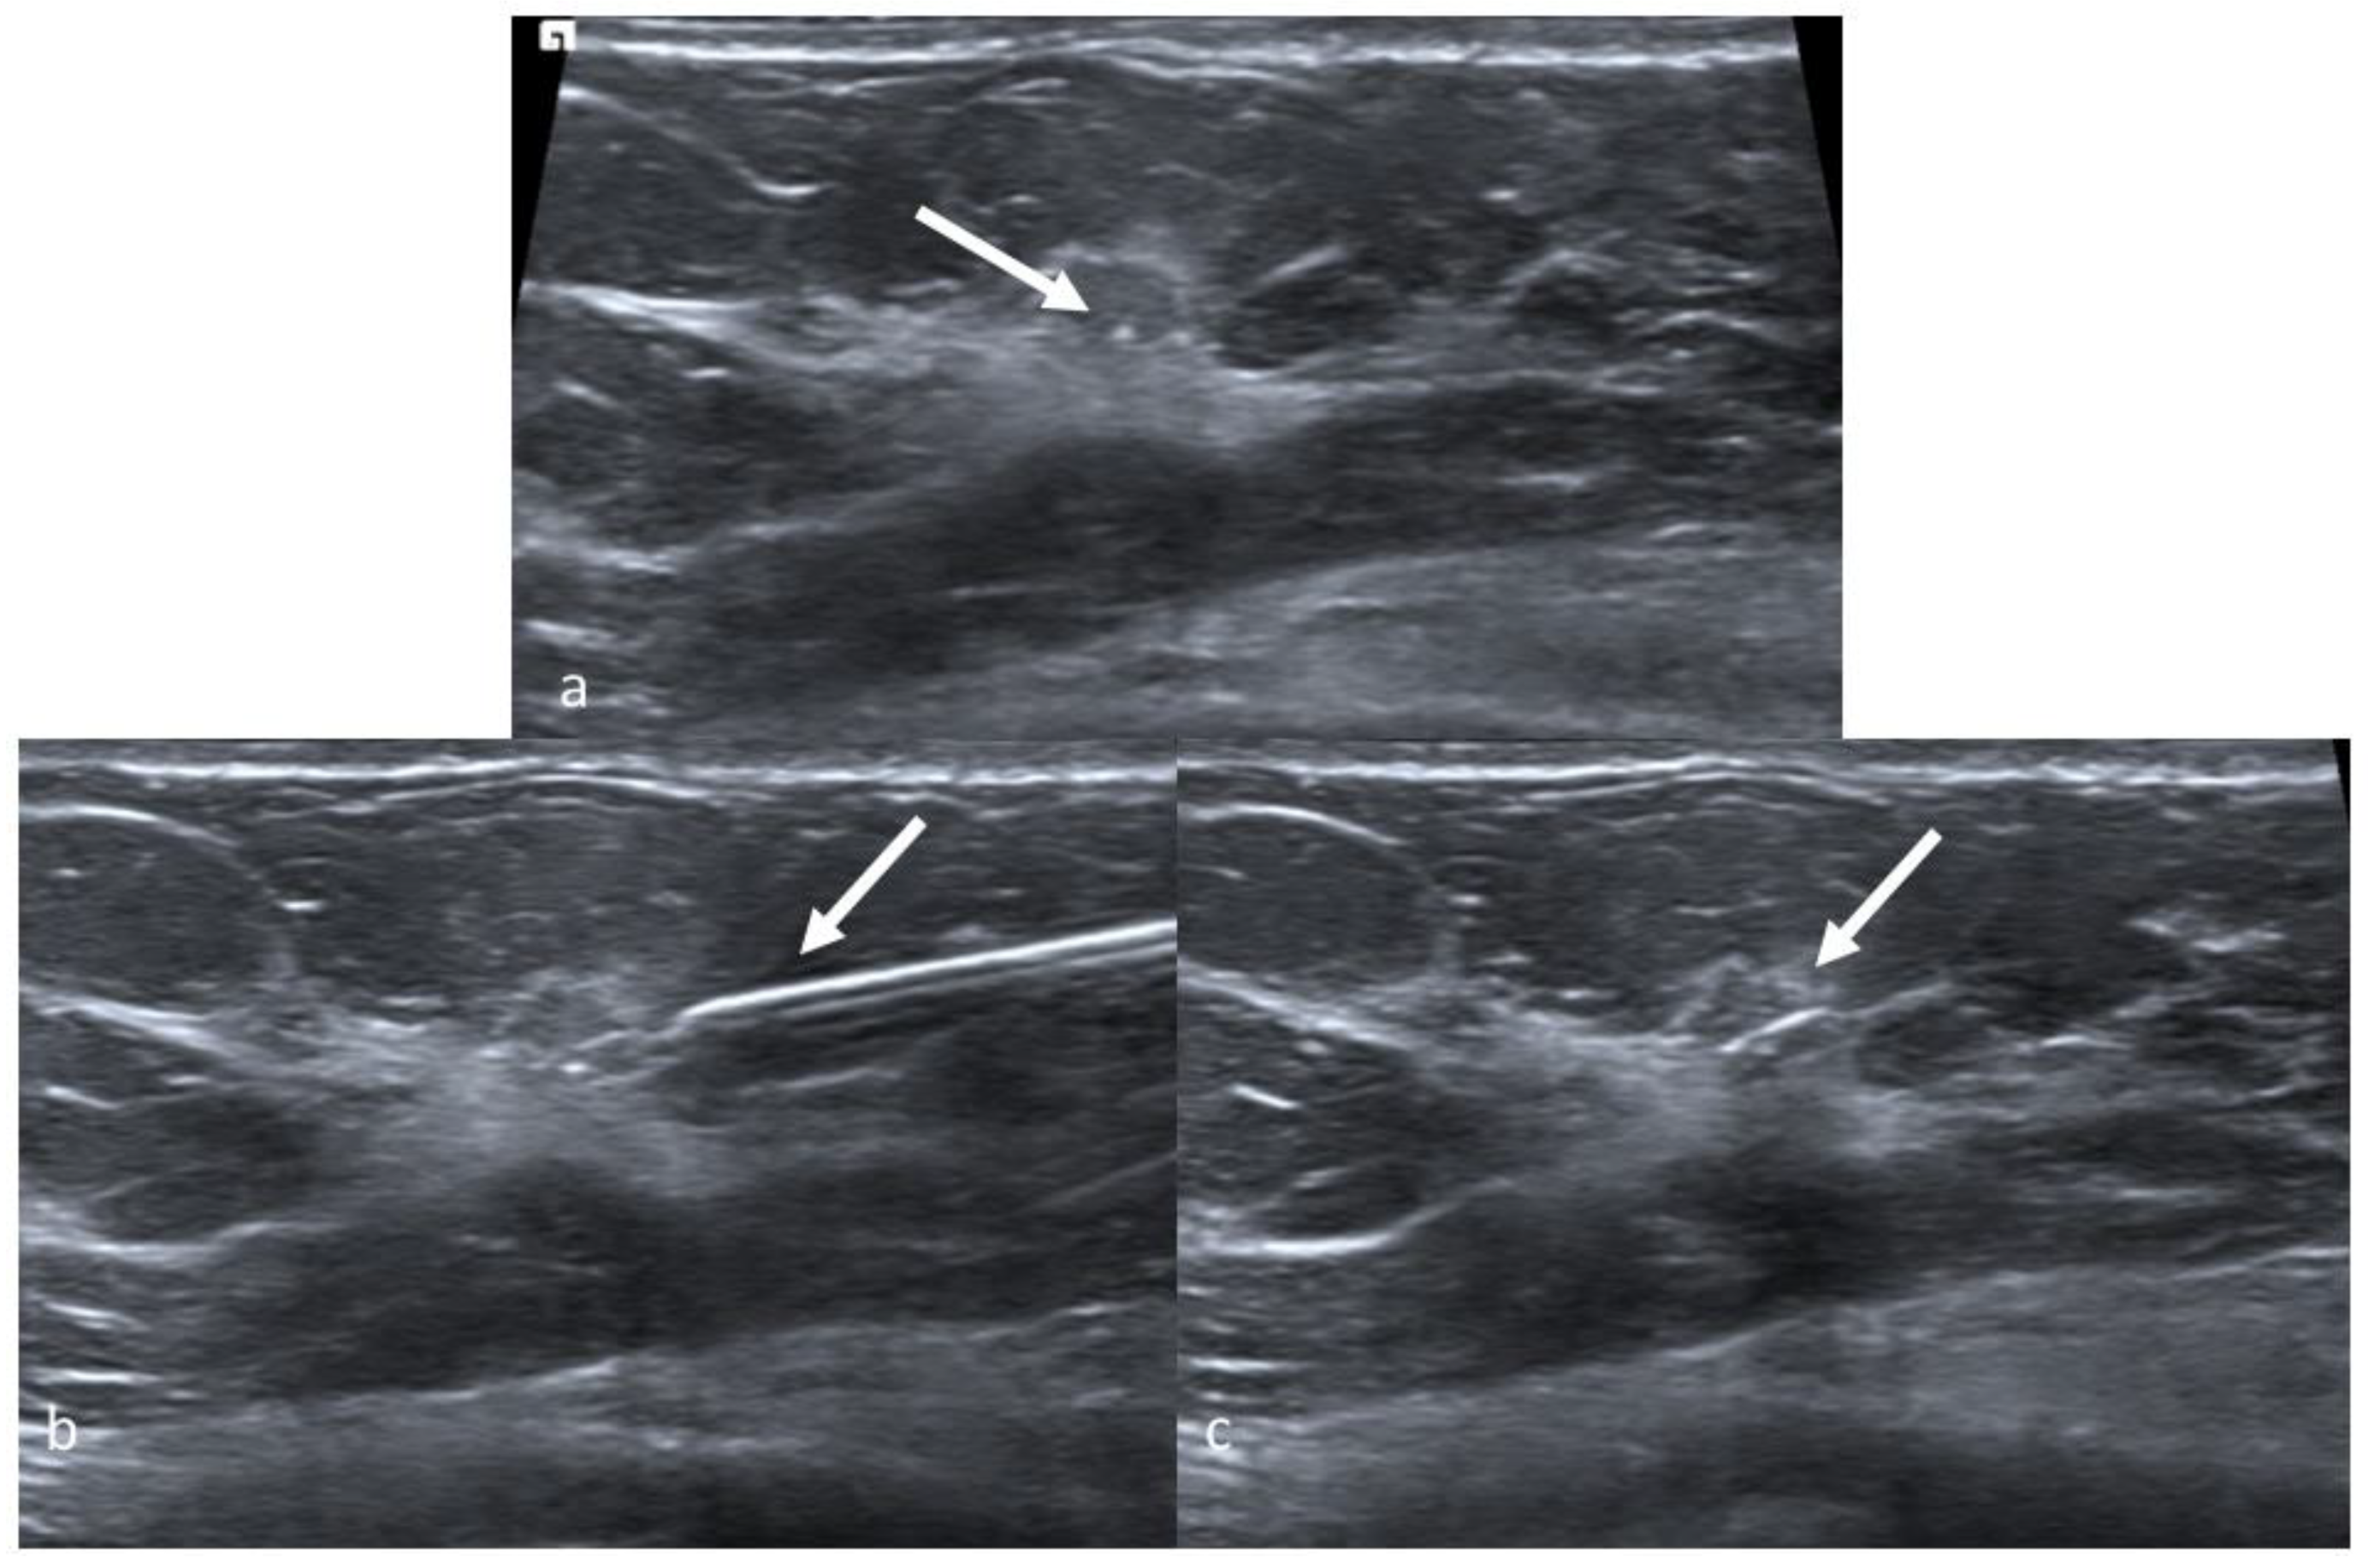

2. Wire Guided Localization